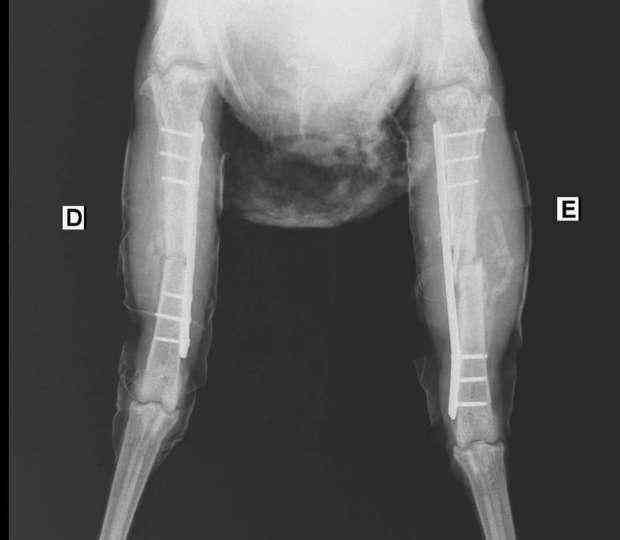

ووفقا لموقع مبتدأ المصري، فقد أصيبت الدجاجة بكسر شديد في قدميها، جعلها تخضع لعملية جراحية استغرقت ساعتين، وتم خلالها تركيب شريحتين و6 مسامير بتكلفة 7 آلاف جنيه.

وأوضح الطبيب الصعوبة التي واجهته أثناء إجراء العملية وهي عدم وجود مسامير وشرائح صغيرة على مقاس رجل الفرخة.

وتضع الدجاجة قدميها في الجبس لمدة شهرين وأثناء هذه الفترة تقوم بعمل جلسات علاج طبيعي، تتراوح بين شهرين و3 أشهر، حتى تستطيع المشي بدون تعرضها لإعاقة حركية، مستخدمة كرسي متحرك لحين فك الجبس.